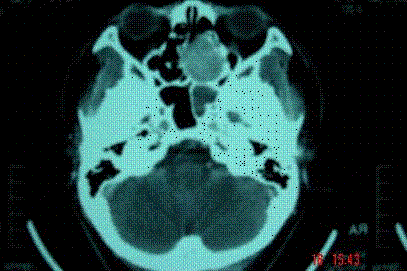

问题 病历摘要: 患者男,37岁,因右鼻塞伴涕中带血4个月入院,患者4个月前始右鼻塞,为间断性,偶有涕中带血,时有流脓性分泌物,并症状渐渐加重。但发病以来患者无头痛、面部麻木和疼痛,无复视及流泪,张口正常。检查:右侧鼻腔总鼻道可见表面光滑、质中、粉红色肿物,触之不易出血。鼻咽黏膜光滑,未见新生物和黏膜糜烂。颈部未及淋巴结肿大。 按UICC1992年分期,该患者为: 提示:通过病理活检,结果为囊性腺样癌